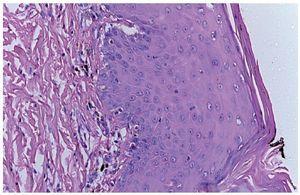

Skin biopsy reported skin with hyperkeratosis and focal parakeratosis. The rest of the epidermis showed dyskeratosis, exocytosis of lymphocytes and neutrophils and formation of intraepidermal vesicles (Figure 4). Band infiltrate consisting of lymphocytes and melanophages with pigment was observed in the junction of the epidermal and papillary dermis (Figure 5). The reticular dermis and subcutaneous tissue showed no alterations.

Figure 4 (A) Intraepidermal vesicle and output of pigment to the papillary dermis. (B) Intraepidermal vesicle.

Figure 5 Panoramic cut of the skin, dermal-epidermal junction with melanophages and output of pigment to the papillary dermis and changes in the stratum corneum of the epidermis.